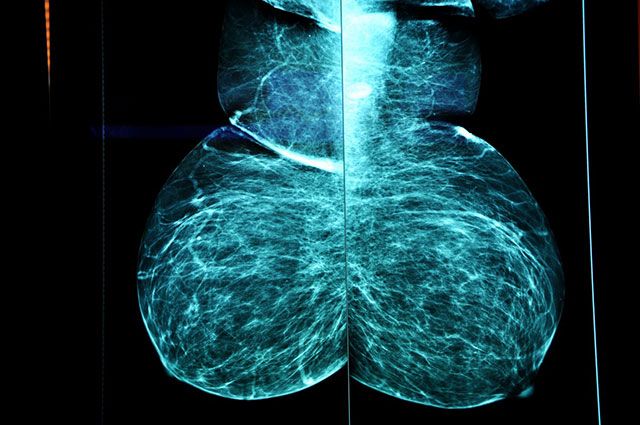

ΨΗΦΙΑΚΗ​ ΜΑΣΤΟΓΡΑΦΙΑ

Με το Senographe Pristina, σας προσφέρουμε την τρισδιάστατη τεχνολογία, γνωστή και ως ψηφιακή τομοσύνθεση μαστού - ΑΙ, με σημαντικά πλεονεκτήματα όπως:

• Ανώτερη διαγνωστική ακρίβεια

• Χαμηλή δόση ακτινοβολίας

• Ανώδυνη εξέταση

• Κατάλληλο για μαστούς με σιλικόνη